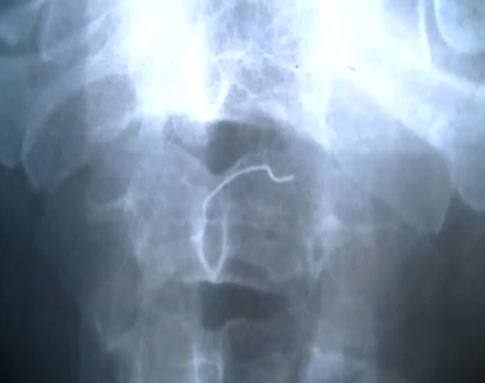

เมื่อสอบถามเรื่องการรักษา ทราบว่า เมื่อช่วงเช้าของวันเดียวกัน แพทย์ได้นำนายวุฒิพงษ์ เข้ารักษายังห้องผ่าตัด ด้วยการนำเครื่องดูดสอดเข้าไปยังช่องทางเดินอาหารบริเวณลำคอ เพื่อนำลวดเย็บกระดาษออกมา หลังจากก่อนหน้าได้ทำการเอกซเรย์แล้วพบว่า มีเส้นเหล็กขนาดเล็ก ลักษณะรูปตัวเอสติดอยู่ ซึ่งแพทย์ใช้เวลารักษาเกือบชั่วโมง จึงนำลวดเย็บกระดาษออกมาได้สำเร็จ